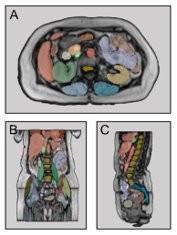

The COMFORT team has addressed this challenge by developing the MRSegmentator, which can automatically identify and outline 40 different body structures in MRI scans with high accuracy.